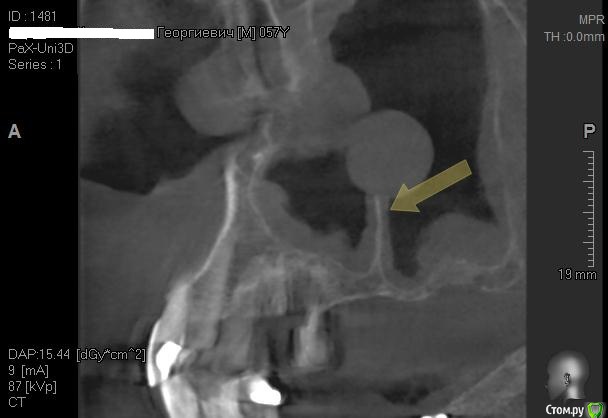

Kostoprav Опубликовано 26 апреля, 2015 Поделиться Опубликовано 26 апреля, 2015 Всем доброго времени суток коллеги!Проблема в следующем- высокая септа и мукоцеле на медиальной стенке пазухи.Мой план: сделать два окна в пазуху по обе стороны от перегородки, аккуратно попробовать отслоить слизистую и если получиться не порвать ее установить два болта не трогая кисту. В случае тотального разрыва мембраны спилить перегородку, убрать мукоцеле, зашить пазуху и повторно пойти на синуслифт через 2 месяца.Хотелось бы услышать Ваши варианты дорогие коллеги. 1 Ссылка на комментарий

колесников Опубликовано 26 апреля, 2015 Поделиться Опубликовано 26 апреля, 2015 Я не рискую ставить одномоментно если собственного объема менее 3 мм. Обычно, в таких случаях ,двухэтапно с разницей в 3 месяца. Ссылка на комментарий

Kostoprav Опубликовано 28 апреля, 2015 Автор Поделиться Опубликовано 28 апреля, 2015 (изменено) Пришлось пойти по варианту №2. слизистая пазухи в месте прикрепления к септе просто расползлась да так что в кучу не собрать. Спилил аккуратно перегородку, убрал мукоцеле (откачал с нее 2 мл. остальное убрал в месте с оболочкой зажимом), заштопал все герметично правда вот теперь думаю, правильно ли сделал что наглухо ушил, может дренаж оставить нужно было? Изменено 28 апреля, 2015 пользователем Kostoprav Ссылка на комментарий

Kostoprav Опубликовано 28 апреля, 2015 Автор Поделиться Опубликовано 28 апреля, 2015 как думаете через какой промежуток времени лучше проводить повторный синуслифтинг, и как отслаиваться в месте окна чтобы опять не порвать слизистую? спасибо! Ссылка на комментарий

Alexey Doc Опубликовано 28 апреля, 2015 Поделиться Опубликовано 28 апреля, 2015 В области окна остро. А по срокам думаю месяца через 3 смело можно Ссылка на комментарий